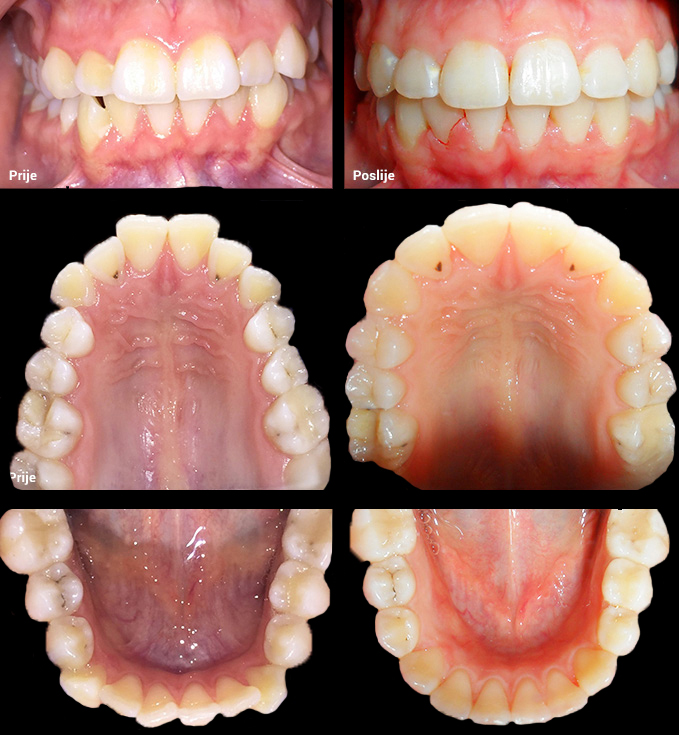

O našoj kvaliteti najbolje govore naši rezultati!

Centar za ortodonciju Petra Džapo